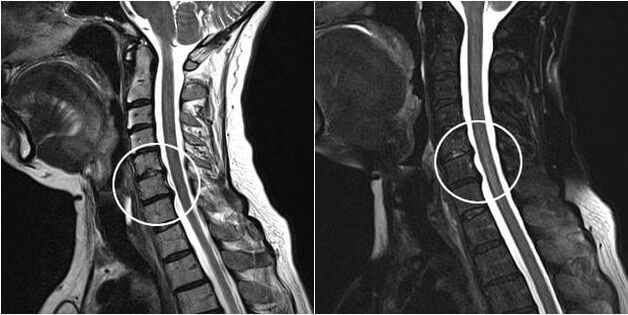

Indications for surgical intervention include the ineffectiveness of conservative treatment, as well as complications of cervical spondylosis, for example, discogenic myelopathy, vertebral artery syndrome and nerve root syndrome.To decompress the spinal cord, blood vessels and spinal roots, the following manipulations are performed: